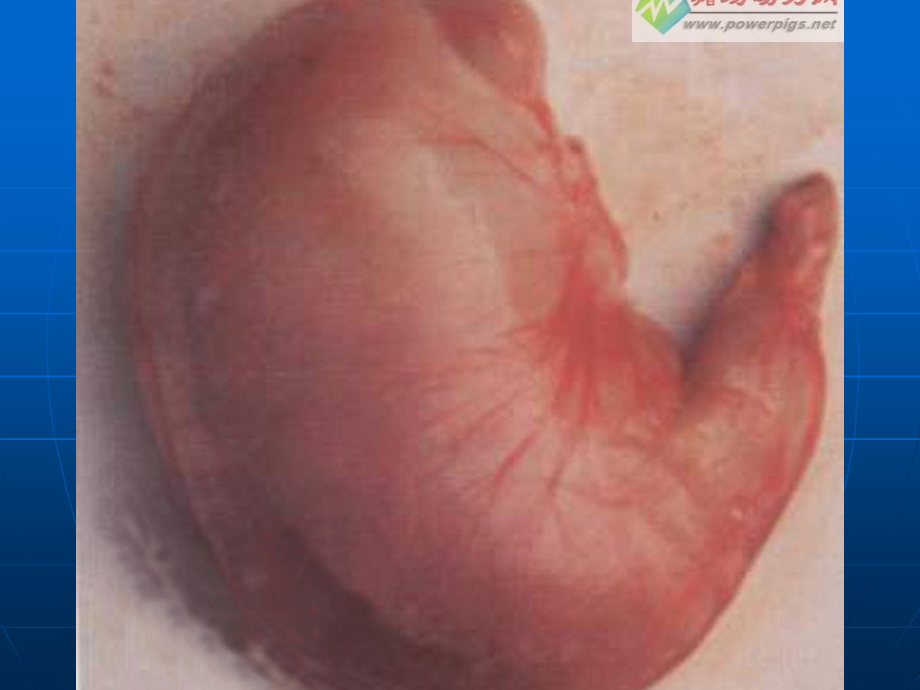

单击此处编辑母版标题样式,*,单击此处编辑母版文本样式,第二级,第三级,第四级,第五级,主讲人:吴丽华,胃炎健康知识讲座,发病率,成人几乎,100,有症状达,30,70,定义:,一、概 述,:,各种病因,慢性胃炎,急性胃炎,胃粘膜的炎症,不同原因所致胃黏膜急性和慢性炎症,胃炎,急性胃炎,慢性胃炎,非萎缩性胃炎,(浅表性胃炎),萎缩性胃炎,(,A,型,,B,型,),特殊类型胃炎,化学性胃炎,放射性胃炎,淋巴细胞性胃炎,肉芽肿性胃炎,嗜酸细胞性胃炎,其他,分 类,分 类:,胃镜分类,胃镜分类,慢性萎缩性胃炎,慢性非萎缩性胃炎,国内分类,急性胃炎,定义,急性胃炎系由不同病因引起的,胃粘膜,急性炎症。病变严重者可累及粘膜下层与肌层,甚至深达浆膜层。,临床上按病因及病理变化的不同,分为急性单纯性胃炎、急性糜烂性胃炎、急性腐蚀性胃炎、急性化脓性胃炎。,其中临床上以急性单纯性胃炎最为常见,而由于抗生素广泛应用,急性化脓性胃炎已罕见。,导致发病的因素很多,:,有,化学,或,物理,的刺激,也有,细菌或其毒素,引起。,化学刺激,主要来自烈酒、浓茶、咖啡、香料及药物,(,如水杨酸盐制剂、消炎痛、保泰松、糖皮质激素等,),,其中急性腐蚀性胃炎多是由吞服强酸、强碱及其他腐蚀剂所致。,物理刺激,如过热、过冷、过于粗糙的食物及,X,线照射,均会损伤胃粘膜,引起炎症性改变。,病因,病因,生物因素,细菌及其毒素,。常见致病菌为沙门菌、嗜盐菌、致病性大肠杆菌等,常见毒素为金黄色葡萄球菌或毒素杆菌毒素,尤其是前者较为常见。,进食污染细菌或毒素的食物数小时后即可发生胃炎或同时合并肠炎此即急性胃肠炎。葡萄球菌及其毒素摄入后合并肠炎此即,急性胃肠炎,。,精神、神经因素。,精神、神经功能失调,各种急重症的危急状态,以及机体的变态,(,过敏,),反应均可引起胃粘膜的急性炎症损害。,胃内异物或胃石、胃区放射治疗均可作为外源性刺激,导致本病。情绪波动、应激状态及体内各种因素引起的变态反应可作为,内源性刺激,而致病。,精神刺激,病因和发病机理,急性应急,胃粘膜缺血、缺氧,粘液、碳酸氢盐分泌减少,前列腺素合成不足,粘膜屏障破坏,糜烂、出血,临床表现,家庭生活中一般在暴饮暴食或食用了污染食物、服对胃有刺激的药后数小时至,24,小时发病。主要为:,上腹痛 正中偏左或脐周压痛,呈阵发性加重或持续性钝痛,伴腹部饱胀、不适。少数病人出现剧痛。,恶心、呕吐 呕吐物为未消化的食物,吐后感觉舒服,也有的病人直至呕吐出黄色胆汁或胃酸。,腹泻 伴发肠炎者出现腹泻,随胃部症状好转而停止,可为稀便和水样便。,脱水 由于反复呕吐和腹泻,失水过多引起,皮肤弹性差,眼球下陷,口渴,尿少等症状,严重者血压下降,四肢发凉。,呕血与便血 少数病人呕吐物中带血丝或呈咖啡色,大便发黑或大便潜血试验阳性。说明胃粘膜有出血情况,。,胆囊炎压痛点,阑尾点,鉴别诊断,:,1,、消化性溃疡穿孔,2,、急性胆囊炎,3,、急性胰腺炎,4,、急性阑尾炎,5,、不典型心肌梗塞,救护措施,急性单纯性胃炎病因简单,治疗起来不复杂,只要按下列措施进行救护,很快恢复正常。,(1),去除病因,卧床休息,停止一切对胃有刺激的饮食和药物。酌情短期禁食,(1-2,餐,),,然后给予易消化的清淡的少渣的流质饮食,利于胃的休息和损伤的愈合。,(2),鼓励饮水,由于呕吐腹泻失水过多,病人在尽可能情况下多饮水,补充丢失水分。以糖盐水为好,(,白开水中加少量糖和盐而成,),。不要饮含糖多的饮料,以免产酸过多加重腹痛。呕吐频繁的病人可在一次呕吐完毕后少量饮水,(50,毫升左右,),,多次饮入,不至于呕出。,救护措施,(3),止痛。应用颠茄片、阿托品、,654-2,等药均可。还可局部热敷腹部止痛,(,有胃出血者不用,),。,(4),伴腹泻、发烧者可适当应用黄连素、氟哌酸等抗菌药物。病情较轻者一般不用,以免加重对胃的刺激。,(5),呕吐腹泻严重,脱水明显,应及时送医院静脉输液治疗,一般,1-2,天内很快恢复。,(6),预防为主,节制饮酒,勿暴饮暴食,慎用或不用易损伤胃粘膜的药物。急性单纯性胃炎要及时治疗,愈后防止复发,以免转为,慢性胃炎,,迁延不愈。,愈后,本病是一种限性的病理过程,病程短,去除致病因素后可以自愈,故除个别由于大出血偶尔可造成严重后果外,即使不经治疗,一般愈后良好。,慢 性 胃 炎,各种原因所引起的胃粘膜慢性炎症性病变,分类,非萎缩性胃炎:胃窦胃炎、胃体胃炎、全胃炎,萎缩性胃炎:多灶萎缩性胃炎、自身免疫性胃炎,特殊类型胃炎:临床少见,1,、,Hp,感染:最主要的病因,病因和发病机理,:,Helicobacter Pylori,电脑模拟,Hp,菌株,(,10,000,),电镜下螺杆状,Hp,幽门螺杆菌,-,螺杆状(电镜),幽门螺杆菌,-,球形(电镜),胃粘膜表面的幽门螺杆菌(电镜),人胃黏膜银染,1000,幽门螺杆菌的发现,1982,年澳大利亚学者,Warren,和,Marshall,首次从人胃黏膜中分离培养出,Hp,Hp,相关疾病,慢性胃炎,Chronic gastritis,消化性溃疡,Peptic ulcer,胃 癌,Gastric carcinoma,胃,MALT,淋巴瘤,MALT lymphoma,幽门螺杆菌,胃癌,胃溃疡,十二指肠溃疡,非溃疡性,消化不良,低度恶性胃,MALT,淋巴瘤,Hp,的流行病学,1994,年,WHO,将,Hp,列为第,类致癌因子,自然人群,病因和发病机理,:,1,.Hp,有鞭毛,在胃内穿过粘液层,移向胃粘膜;,2,.,有粘附素能贴紧上皮细胞而长期定居于胃窦粘膜小凹处及其邻近上皮表面繁衍,不易去除;,病因和发病机理,:,3,.,有尿素酶,能分解尿酸产生,NH3,,既能保持细菌周,围的中性环境,又能损伤上皮细胞膜;,4,.,空泡毒素,VagA,:损伤上皮细胞,;,细胞毒素相关基因,CagA,蛋白能引起强烈的炎症反应;,5,.,菌体胞壁可作为抗原产生免疫反应。,病因和发病机理,:,壁细胞,胃酸,壁细胞损伤,壁细胞抗体,壁细胞减少,胃酸分泌,或缺乏,内因子抗体,维生素,B,12,吸收不良,恶性贫血,2,、自身免疫反应,3,、十二指肠液反流:胆汁反流性胃炎。,病因和发病机理,:,幽门括约肌松弛十二指肠液(胆汁、胰酶)反流,削弱胃粘膜屏障胃液、胃蛋白酶损害。,4,、其他因素:,幽门螺杆菌感染增加胃黏膜对环境的易感性,饮食因素:高盐、缺乏新鲜水果。,病因和发病机理,:,部分无症状。部分消化不良,上腹不适、饱胀,餐后明显;不规律上腹痛,反酸,嗳气,食欲不振,恶心,A,型胃炎可明显厌食,体重下降,贫血,舌炎、舌萎缩(镜面舌)和周围神经病变如四肢感觉异常,常见病,男性略多于女性,任何年龄均可发病,发病率随年龄增加,临床表现,1,、血清学检查,2,、维生素,B,12,吸收试验,实验室检查:,Co57,Co58,Co57,维生素,B12+,内因子,Co58,维生素,B12,3,、胃镜及活检:,最可靠的诊断办法。,胃镜诊断办法分七类:,充血渗出性 出血性 平坦糜烂 隆起糜烂 萎缩性 皱襞增生性 反流性,实验室检查:,胃镜检查及活检:,非萎缩性胃炎(浅表性胃炎),萎缩性胃炎,粘膜红白相间,,红为主,粘液分泌增多,散在糜烂、出血,浅表炎性细胞浸润,腺体完整,胃镜,病检,粘膜苍白或灰白色,,或红白相间,以白为主,皱襞变细而平坦,粘膜层变薄,血管透见,粘膜层及粘膜下层,炎性细胞浸润,腺体部分或完全消失,,肠上皮化生,正常的胃粘膜,胃粘膜水肿,出血性胃炎,非萎缩性胃炎,萎缩性胃炎,浅表性胃炎,浅表性胃炎内镜下表现有:黏膜充血、水肿、黏液分泌较多、可有出血点和少量糜烂。,Hp,感染的诊断方法:,侵入性方法,侵入性检测方法,:,依赖于胃镜活检,快速尿素酶试验,(RUT),胃黏膜直接涂片染色镜检,胃黏膜组织切片染色镜检(如,W-S,银染、改良,Giemsa,染色、甲苯胺蓝染色、免疫组化染色),细菌培养,基因检测方法,(,如,PCR,、寡核苷酸探针杂交等,),免疫检测尿素酶,(IRUT),(,内镜与活检钳消毒不严格可造成医源感染,),Hp,感染的诊断方法:,非侵入性方法,非侵入性检测方法,:,不依赖内镜检查,13,C,或,14,C,尿素呼气试验,(UBT),15,尿氨排泄试验,粪便,Hp,抗原检测、,血清及分泌物(唾液、尿液等)抗体检测,基因芯片和蛋白芯片检测,(,病人依从性较好,),实验室检查:,方法,(,2,)常用,Hp,诊断方法的优缺点:,敏感性,特异性,优点,缺点,(%),(%),组织学,细菌培养,Hp-RUT,13,C-UBT,14,C-UBT,血清学,PCR,93-99,70-92,89-98,90-100,90-100,88-99,96-100,95-99,100,93-98,89-100,89-100,86-99,96-100,观察病变,金标准、,简便、快速,无侵袭、无放射,无侵袭性,简便,简便、可检测致病基因,有侵袭性,需熟练技术,假阴性,价格昂贵,有放射性,不反映活动,病史无特异性,确诊:靠胃镜及病理检查,幽门螺杆菌检查有助于病因诊断,自身免疫性胃炎:,应检查相关抗体和血清胃泌素。,诊断:,1,、消化性溃疡,2,、胃癌,3,、功能性消化不良,4,、慢性胆囊炎,5,、钩虫病,鉴别诊断,:,治疗,烟酒咖啡醋蒜葱,,粗熏腌咸热匆匆,,消炎对症促排空,,保护黏膜促再生,,C.E,、锌硒、增生平,,叶酸理疗练气功。,1,、消炎:消炎,HP,:,PPi+,两种抗生素(阿莫西林、四环素、痢特灵),CBS+,两种抗生素(克拉酶素、灭滴灵),四联:,PPi+CBS+2,种抗生素,,Bid,一周疗法 消除慢性感染灶,2,、对证促排空:胀、反流、疼、可制酸、胃动力药,胆汁反流:氢氧化铝凝胶,达喜(铝磺酸镁片),3,、黏膜保护:硫糖铝、前列腺素制剂、,CBS,4,、促再生:,CE,胃肠宁,100,400mg/,日,5,、胃黏膜肠化 不典型增生者,C.E,叶酸、锌、硒。,胡罗卜素、定期随访。增生平、胃复春,6,、预防性手术:适于重度不典型增生者,7,、疼:元胡止疼片、六味木 香 胶囊、心胃丹,8,、焦虑:气功、谷维素、阿米替临、多 虑 平、左洛复、百忧解。,9,、恶贫:,VitB12,、叶酸,护理:,1,、祛除诱因:酒、药、感染源,2,、饮食:禁食、流质、平流,3,、手术,健康教育:戒酒、药(饭后)、卫生(剩饭),饮食 定时定量、无刺激、戒烟、酒,慢性胃炎最好吃什么,注重软、烂、消化:食用的主食、蔬菜及,鱼肉,等荤菜,特别是豆类、花生米等硬果类都要煮透、烧熟使之软烂,便于消化吸收,少吃粗糙和粗纤维多的食物,要求食物要精工细作,富含营养。,保持新鲜、清淡:各种食物均应新鲜,不宜存放过久食用。吃新鲜而含纤维少的蔬菜及水果,如,冬瓜,、,黄瓜,、,番茄,、土豆、,菠菜,叶、小,白菜,、,苹果,、梨、,香蕉,、,橘子,等。吃清淡少油的膳食。清淡膳食既易于消化吸收,又利于,胃病,的康复。,慢性胃炎不宜吃什么,慢性胃炎患者忌食烈性酒,(,其他酒类也应少饮或不饮,),、香烟、浓,茶,、咖啡、,辣椒,、芥末等刺激性强的调味品。不宜吃过甜、过咸、过浓、过冷、过热、过酸的汤类及菜肴,以防伤害胃黏膜。大量饮用碳酸饮料也会对胃黏膜造成不同程度的损害。,在我国,Hp,对抗生素耐药情况,在我国,Hp,对抗生素耐药情况,甲硝唑的耐药率,70%,克拉霉素的耐药率,20%,阿莫西林的耐药率为,2.7%,慢性非萎缩性胃炎,(浅表性胃炎),预后,:,痊愈,萎缩性胃炎,癌变,1,、注意饮食卫生。,2,、避免对胃有刺激性的食物和药物。,3,、戒烟酒等。,预防,:,改变饮食习惯。,Thanks,